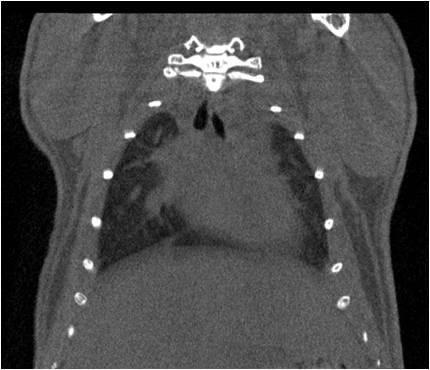

肺轉(zhuǎn)移

小鼠模式,22.5μm像素

正常

正常.jpg

8天                                                                  14天

無造影劑注入                                     造影劑注入

心血管

胸部和心血管的層析成像                                       胸部和心血管的3D圖像